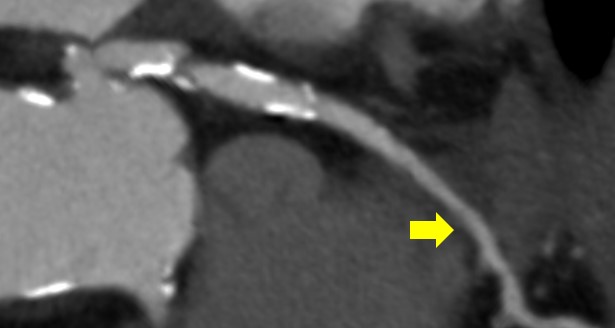

冠動脈CTA撮影後のDelayでのAorta撮影の画像を下記に提示します。通常の120kVpで撮影された画像と比較して、TEDLの画像の方が造影コントラストが得られますので、当院では、全例でTEDLを活用しています。

実際に、冠動脈CTA施行時にAAAとCIAに壁在血栓のある症例ですがdelay撮影でも十分な存在確認ができています。

Ascend_ayase13.png

TEDLを活用した血栓評価